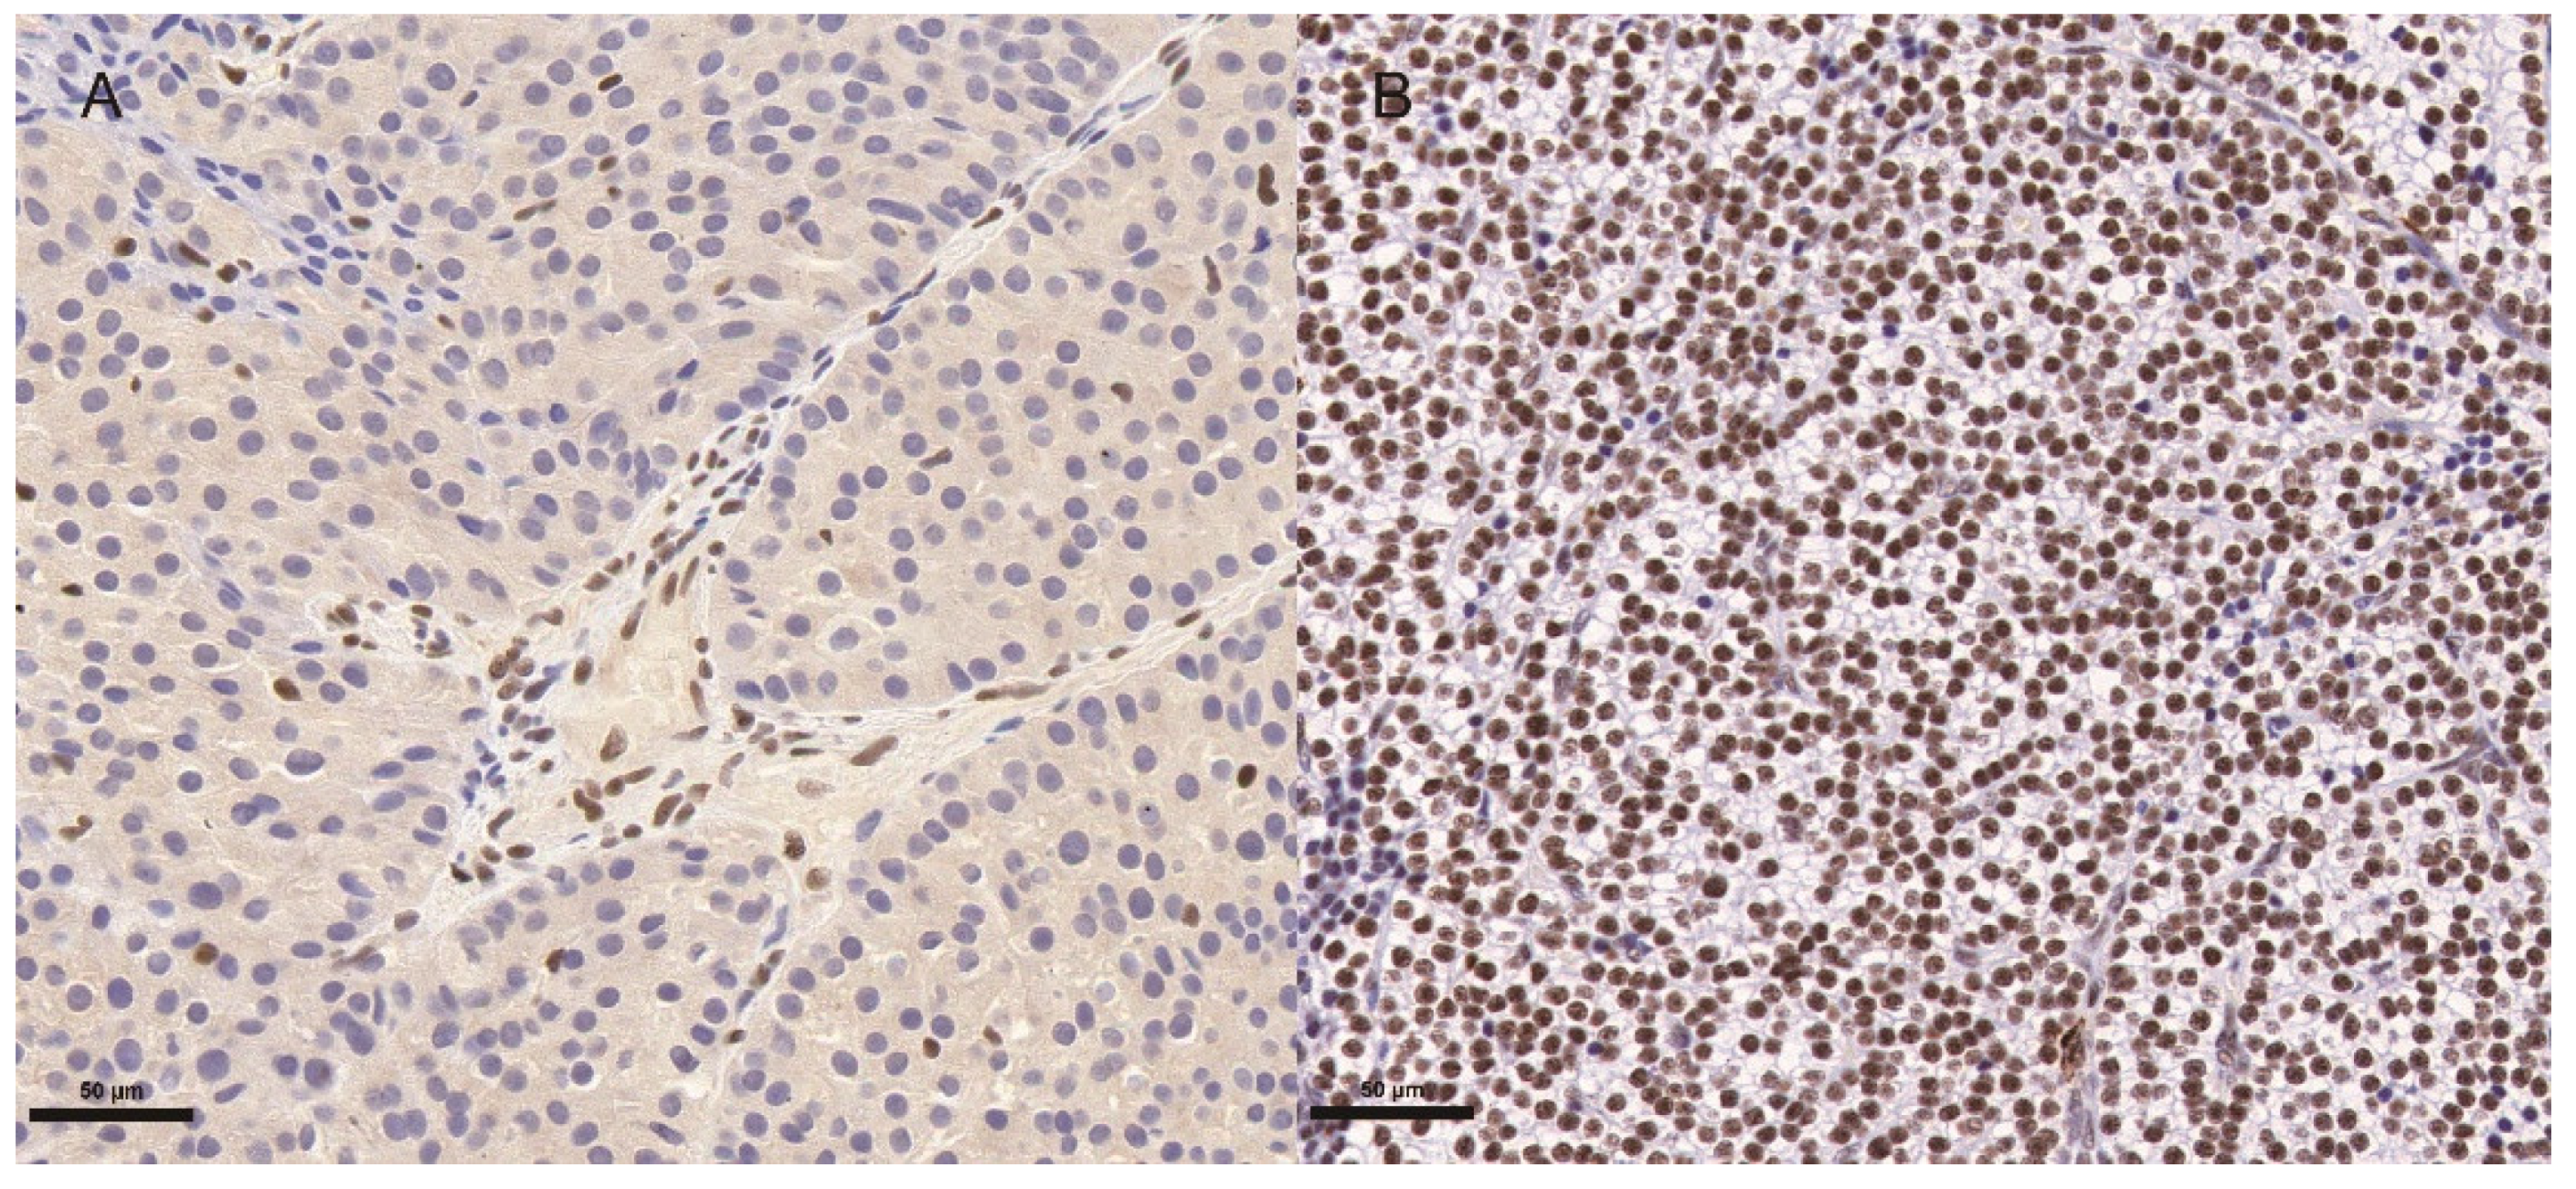

| CDC73 abnormalities (%) (n = 54) Parafibromin staining loss (%) (n = 50) CDC73 mutations (%) (n = 35) | 53.7% 52% 51.4% |

| Ki67 index ≥ 5% of initial tumor specimens (%) (n = 52) | 69.2% |